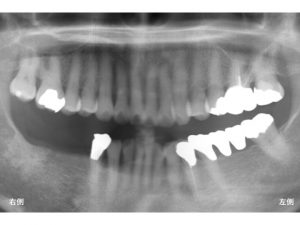

初診時に下顎右側の奥歯が3歯分欠損していました。

通常3歯欠損ですから3歯分の歯を作成します。

インプラント治療の場合、3本のインプラントが必要ということではなく、

通常3歯欠損の場合には、

2本のインプラントを埋入し、

3歯分の被せ物を作成するインプラントブリッジとすることが多いです。

しかし、骨の吸収状態が悪く、

短いインプラントしか埋入できなかったり、

噛み合わせの問題があった場合には、

インプラントの本数を増やして

3本のインプラントとすることもあります。

今回のケースでは、3歯分の歯は作成しない治療計画となりました。

具体的には

2歯分の被せ物を作成する方法です。

つまり一番奥歯には、何も行わないという計画です。

以下がインプラント手術が終わった直後です。